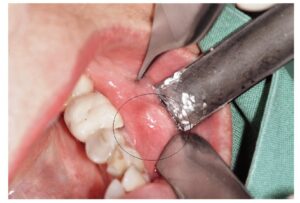

روش تشخیصی استاندارد که به آن بیوپسی فک و صورت کودکان میگویند که در آن جراح فک و صورت با ابزارهای مخصوص قطعهای از بافت ناحیه درگیر را جدا میکند. این بافت میتواند از لثه، استخوان فک، زبان یا مخاط دهان باشد. هدف اصلی از نمونه برداری توده فک کودکان رسیدن به یک تشخیص سلولی دقیق است.

روش نمونه برداری تومور فک در کودکان معمولا به دو صورت کلی انجام میشود. یا فقط بخشی از توده برای تشخیص برداشته میشود که به آن بیوپسی اینسیژنال میگوییم یا کل توده همراه با حاشیه سالم برداشته میشود که بیوپسی اکسیژنال نام دارد.

انتخاب بین این دو روش به نظر جراح و سایز ضایعه بستگی دارد. در مواردی هم ممکن است از نمونه برداری سوزنی فک کودکان استفاده کنیم که کمتر تهاجمی است.